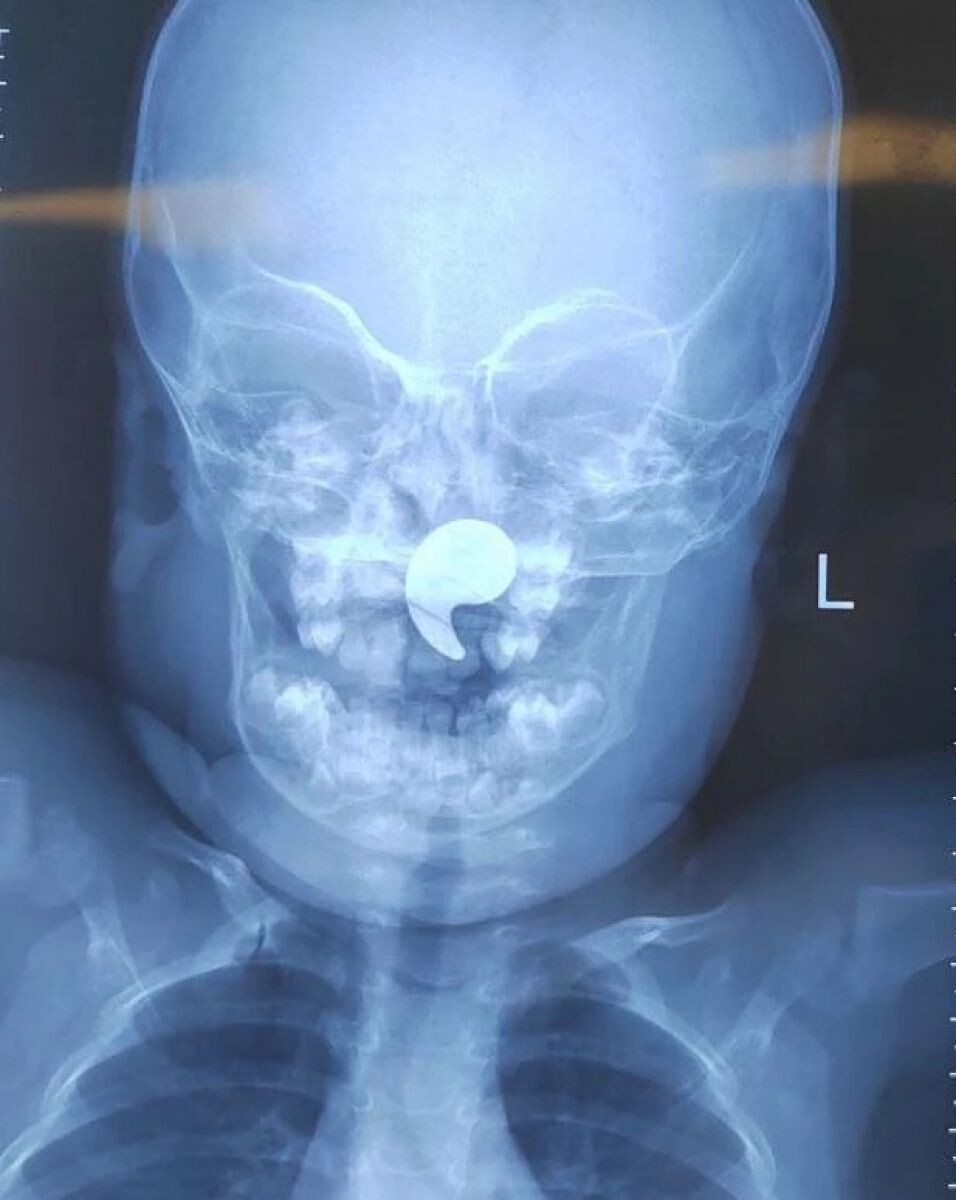

В Воронежскую областную больницу №1 обратились родители полуторагодовалой девочки. Они рассказали, что малышка играла магнитом в форме запятой, а затем начала давиться. После того как мать попыталась извлечь его пальцем, магнит сдвинулся в носоглотку. Позже у ребенка появилась боль в горле, отказ от еды и обильное слюнотечение. Об этом сообщили в пресс-службе Минздрава Воронежской области.

Малышке сделали рентгеновский снимок и подтвердили наличие инородного тела. Ребенка госпитализировали в оториноларингологическое отделение. Под общим наркозом и под контролем эндоскопа магнит был успешно извлечен. Уже на следующие сутки девочку выписали домой под наблюдение педиатра.